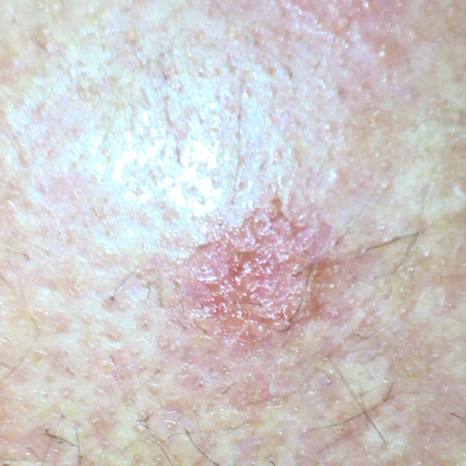

La kératose actinique donne souvent à la peau une couleur brun-rougeâtre, avec des zones surélevées et une surface rugueuse et croûteuse. En effet, la traduction littérale de kératose actinique signifie cornification de la peau induite par le soleil. La croûte est souvent de couleur blanche, mais elle peut aussi être jaune ou brune. Les taches ont souvent une taille de quelques millimètres à quelques centimètres. Elles ne présentent généralement aucun symptôme, parfois une sensation de gêne ou de démangeaison. Cette anomalie cutanée est souvent observée sur le visage, le dos des mains, les bras, les jambes, le décolleté, le pavillon de l'oreille ou, chez les hommes chauves, sur le cuir chevelu. Il y a généralement plusieurs KA sur la peau.

Exemple de photo de kératose actinique